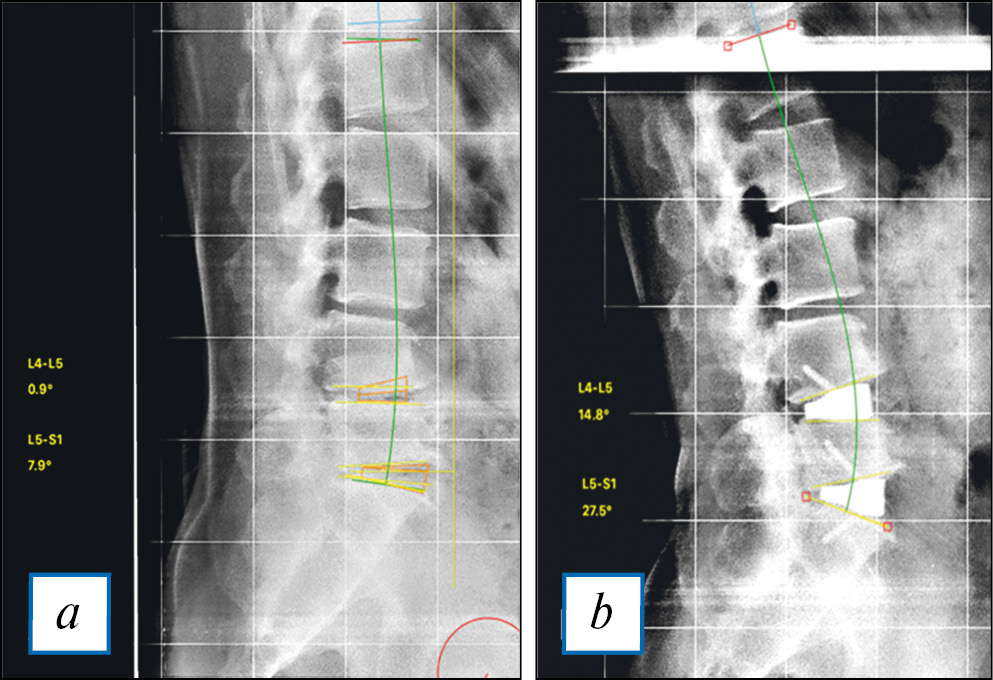

В 2020 г. А.А. Денисов и соавт. подтвердили, что применение лордозирующих кейджей с углами 20–30° значительно увеличивают сегментарный лордоз и лордоз поясничного отдела позвоночника (рис. 4) [57].

Рис. 4. Измерение сегментарного и лордоза поясничного отдела позвоночника.

Примечание. a — рентгенограмма пациента до операции (слева представлены значения углов L5–S1 = 7,9, L4–L5 = 0,9); b — рентгенограмма того же пациента после установки индивидуальных межтеловых имплантатов (значения полученных углов сегментарного лордоза: L5–S1 = 27,5; L4–L5 = 14,8) (данные А.А. Денисова).

Fig. 4. Measurement of segmental lumbar lordosis.

Note. a — a radiograph of a patient before the surgery (on the left, the angles L5-S1=7.9, L4-L5=0.9 are displayed); b — a radiograph of the same patient after installation of individual intervertebral implants (the angles of segmental lordosis are L5-S1=27,5, L4-L5=14,8). (Own data of А.А. Denisov).

В 30 случаях были имплантированы кейджи с индивидуальным, заранее запланированным углом лордоза. Степень полученной коррекции сегментарного лордоза практически была идентична прогнозируемым результатам для группы ALIF. Авторы связывают полученные результаты как с техникой установки имплантатов, которая в случае использования вентрального доступа требует полного освобождения передней продольной связки, так с наличием конструктивных преимуществ используемого имплантата (форма клина).